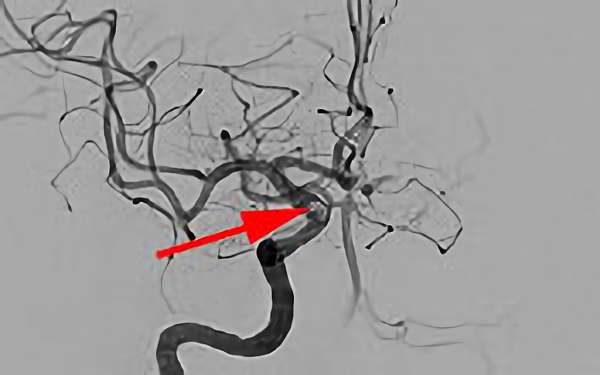

No.1631 手術後